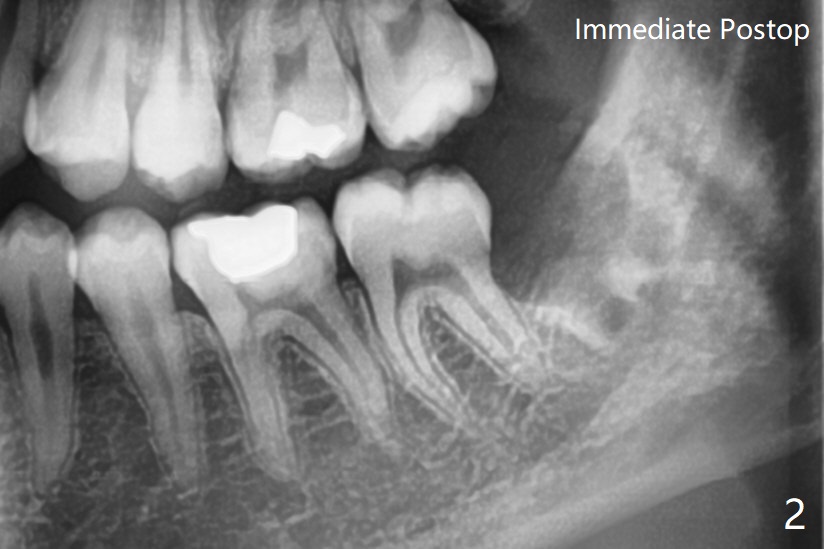

16岁男孩

左下智齿疼痛(图一),截骨后牙齿容易松动,然后切断两次,顺利拔除,放置Osteogen Plug,4-0 铬羊肠线缝合(图二)。5个月后另外三个智齿拔除(右下放置胶原塞;上智齿拔除盲目,困难,稍微早些),左下智齿牙槽窝愈合(图三);近中牙槽嵴重建。